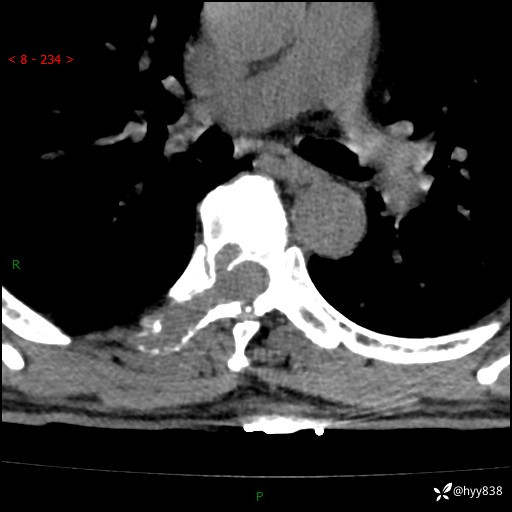

辅助检查:CT MRI

胸椎MRI平扫(sag T1WI+T2WI)